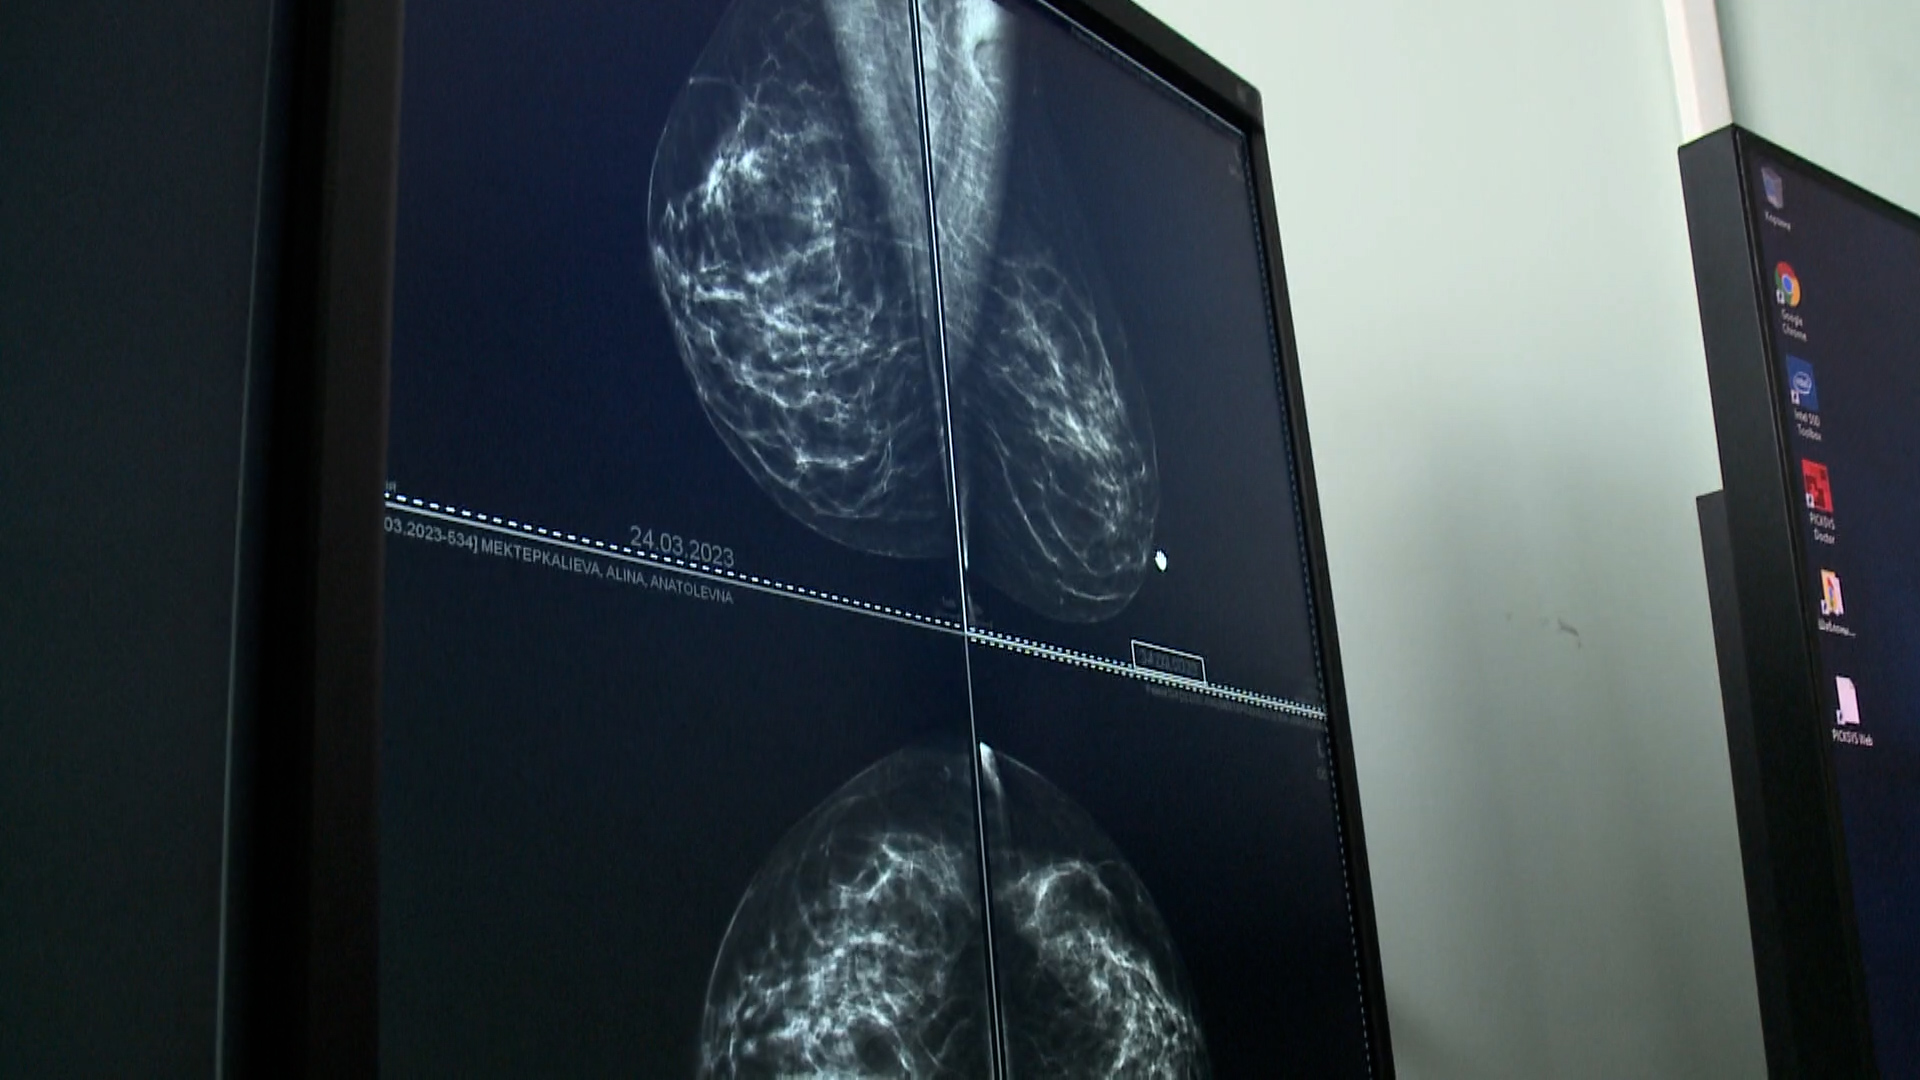

Пост принял. В таркосалинской центральной районной больнице заступил на службу новый доктор. В штате медучреждения теперь работает врач-онколог Роберт Мирсояпов. На новом месте работы его встретили радушные коллеги, доктор даже успел посетить отдаленные поселения.

На новом месте Роберт работает почти 2 месяца, но уже смог принять пациентов в Ханымее и Харампуре. С появлением второго онколога больница чаще может проводить профилактические работы с населением, отправлять врачей в отдаленные поселения.